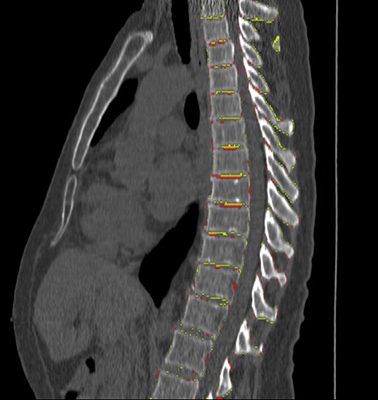

3.3 Iterative instance segmentation

The iterative segmentation process is illustrated in Figure 2. This process follows either a top-down or bottom-up scheme, i.e., the vertebrae are not segmented in random order but successively from top to bottom, or vice versa. The network learns to infer from the memory patch which vertebra to segment in the current patch. If the memory is empty, i.e., no vertebra has been detected yet, the network segments the top-most or bottom-most vertebra that is visible in the patch, depending on the chosen direction of traversal. Otherwise, the network segments the first following not yet segmented vertebra, even if multiple unsegmented vertebrae are visible. Other vertebrae that are the second or third not yet segmented vertebra in the direction of traversal are disregarded until they become the first not yet segmented vertebra themselves in a later iteration. Each instance of the network therefore has a fixed direction of traversal.

The patch size is chosen large enough to always contain part of the following vertebra when a vertebra is in the center of the patch. This enables utilizing prior knowledge about the spatial arrangement of the individual instances to move from vertebra to vertebra. The FCN iteratively analyzes a single patch centered at , where denotes the iteration step. Initially, the patch is moved over the image in a sliding window fashion with constant step size , searching for the top-most vertebra when using a top-down approach, or the bottom-most vertebra when using a bottom-up approach. As soon as the network detects a large enough fragment of vertebral bone, at least in our experiments, the patch is moved toward this fragment. The center of the bounding box of the detected fragment, referred to as , becomes the center of the next patch:

Even if initially only a small part of the vertebra is visible and detected in the patch, centering the following patch at the detected fragment ensures that a larger part of the vertebra becomes visible in the next iteration. Eventually, the entire vertebra becomes visible, in which case the patch position converges because no additional voxels are detected anymore that would affect , and hence . We detect convergence by comparing the current patch position and the previous patch position , testing whether they still differ by more than on any axis. Occasionally, the patch position does not converge but keeps alternating between positions that differ slightly more than the threshold . We therefore limit the number of iterations per vertebra. When this limit is reached, we assume that the patch has converged to the position between the two previous patch positions and we accordingly move the patch to . In our experiments, was set to , to half the patch size and the maximum number of iterations to .

Once the position has converged, the segmented vertebra is added to the output mask using a unique instance label and the segmentation mask obtained at this final position. Furthermore, the instance memory is updated. In the following iteration, the network analyzes the same patch again. The updated memory prompts the network to detect a fragment of the following vertebra and the patch is moved to the center of the detected new fragment, repeating the segmentation process for the next vertebra. Should no fragment of the following vertebra be immediately visible, traversal reverts to a sliding window motion until the next vertebra is found. The entire process continues until no further fragments are found, i.e., until all visible vertebrae are segmented.